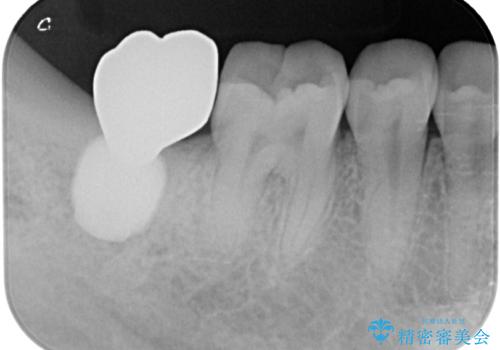

抜歯された骨の穴は、インプラント埋入時にはまだ大きな窩洞となっていましたが、径の大きいワイドインプラントを選択することで、埋入時に十分な安定を獲得することができました。

後方には欠損が残っていたため、補填材を填入しました。

術後にインプラントが骨から脱落することがありますが、特筆するトラブルなどなく、最短の3ヶ月で治療を終えることができました。